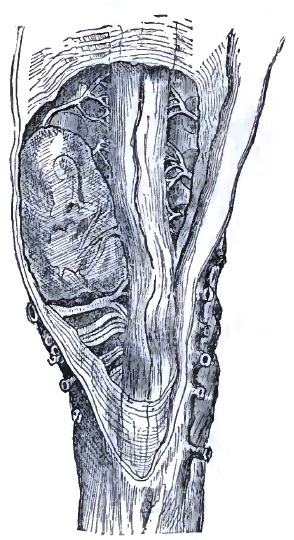

| 46. | SARCOMA PRESSING CERVICAL CORD (E. LONG FOX) |

| 47. | SARCOMA OF LOWER CERVICAL CORD |

| 48. | THE SAME AS FIG. 47 |

| 49. | THE SAME AS FIG. 47 |

| 50. | THE SAME AS FIG. 47 |